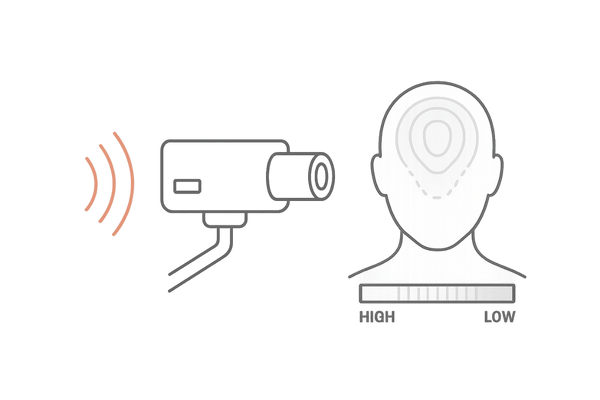

サーモグラフィー検査は、物体から放射される赤外線を検知し、その表面温度の分布を映像として表示する技術です。医療分野では、血行状態の評価や炎症の診断などに広く活用されています。

これを頭皮に応用することで、これまで主観的な判断に頼りがちだった頭皮の血行状態を、客観的なデータとして捉えることができます。

すべての物体は、その温度に応じた赤外線を放射しています。

サーモグラフィーのカメラは、この目に見えない赤外線を特殊なセンサーで捉え、温度の高い部分を赤や黄色、低い部分を青や緑といったように、色の違いで視覚的に表現します。

人体に何かを照射するのではなく、体から自然に放出される赤外線を捉えるだけの受動的な検査なので、痛みや副作用の心配は全くありません。

X線検査のような放射線被曝のリスクもなく、お子様からご年配の方まで、どなたでも安心して受けられます。検査自体も、専用のカメラで頭部を撮影するだけで、数分程度で完了します。